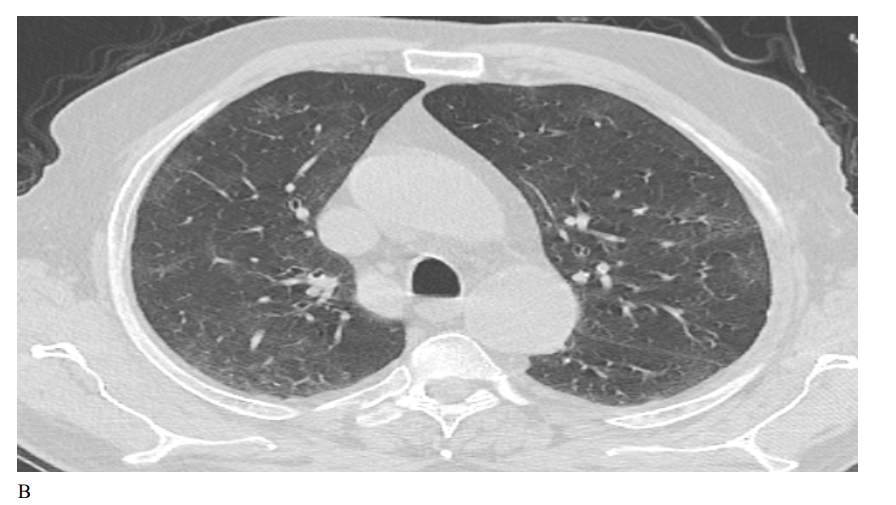

Figure 1: Male patient in favipiravir group shows (A) bilateral lung infiltration with areas of ground glass opacities and peripheral pleural based consolidation, Covid severity score 12, Corad 5. (B) After 3 months of therapy, Improvement of bilateral pulmonary infiltrates with residual basal ground glass opacities, Covid severity score 5.